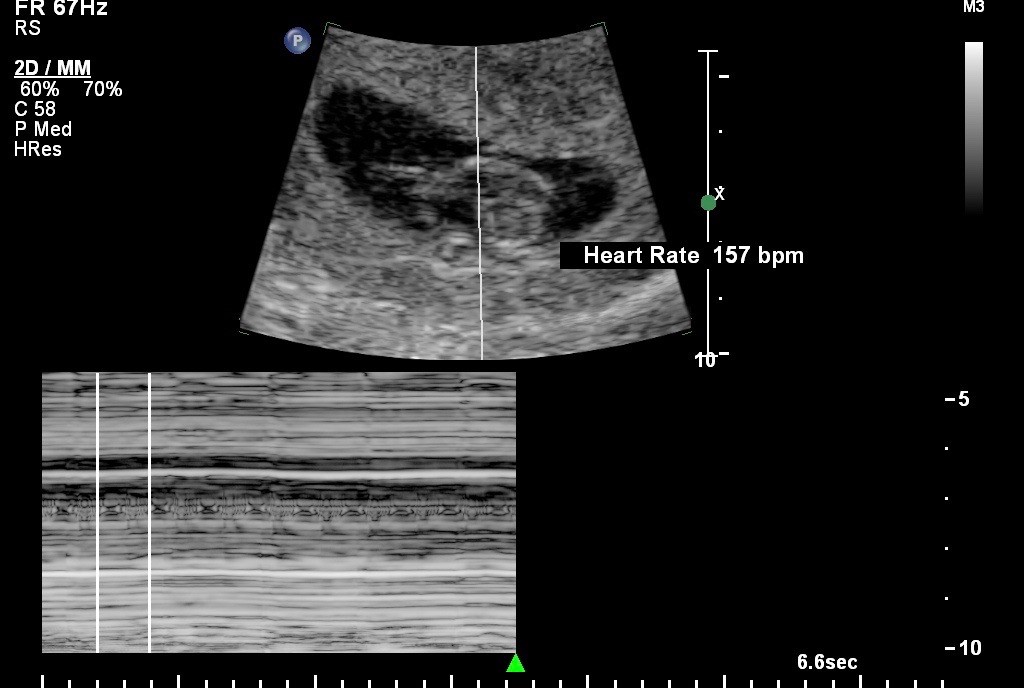

According to a study published in the medical journal Ultrasonography last year, cardiac activity is seen when the embryo is 1-2 mm in size. The fetal heart rate gradually increases with gestational age from approximately 110 beats per minute (bpm) at 6.2 weeks to approximately 159 bpm at 7.6-8.0 weeks.[1] The American Association of Prolife Obstetricians and Gynecologists (AAPLOG) in its patient guide pamphlet states, “At about 22 days after fertilization your child’s heart begins to circulate his or her own blood, unique from your own, and has a heartbeat that can be detected on ultrasound.”

The embryonic heartbeat is the first sign of early pregnancy on ultrasound, which can be visualized in transvaginal ultrasound at approximately 5 weeks gestation. The American Pregnancy Association states that the presence of an embryonic heartbeat is an assuring sign of the health of the pregnancy.[4] The heart of the embryo continues to develop over the next several weeks. It is fully formed around 10 weeks gestation.[5]

Cardiovascular development in a human embryo occurs between 3 and 6 weeks after ovulation. Cardiac function is the first sign of independent cardiac activity that can be explored with non-invasive techniques such as Doppler ultrasound.

Women making pregnancy choices should have at least one scan for accurate fetal heart rate and assessment of viability, placement, and dating of the pregnancy. Ideally, they would have access to ultrasound before six weeks and beyond the first trimester.